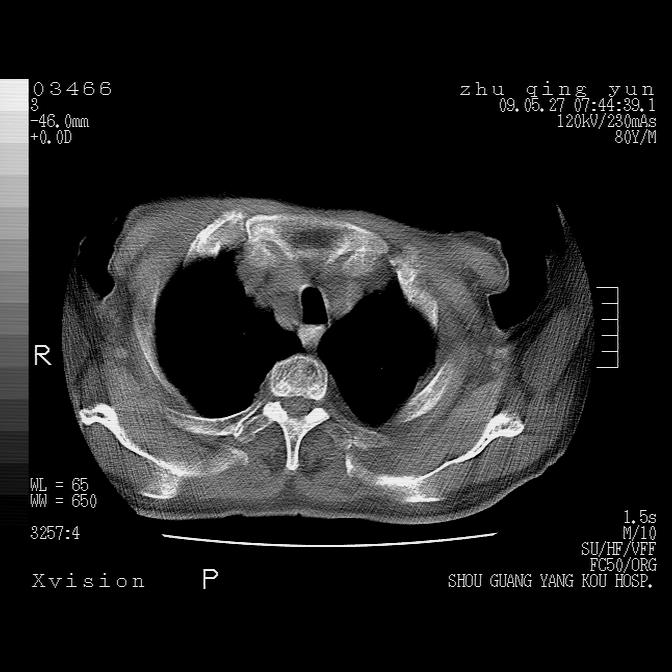

病人男性,年龄80,气喘来院,其他病史不太详细,1月前有过恶心,呕吐,在当地人民医院做过钡餐,诊断胃炎,

1)考虑左肺中央型肺癌并阻塞性肺炎,后下纵隔受侵伴纵隔淋巴结转移。2)双侧少量胸腔积液,胸膜增厚。3)心包积液。

左肺下叶见多发片状及结节状病灶,左肺基底段支气管闭塞,纵隔内见多发淋巴结肿大,纵隔向左侧移位,左侧胸廓变小。应该是左肺下叶中心型肺癌,纵隔淋巴结转移,左侧肺内转移,左肺基底段肺不张,阻塞性肺炎。

1)考虑左肺中央型肺癌并左肺下叶阻塞性肺炎、不张;左胸膜腔积液、心包积液、纵隔淋巴结转移;癌肿累及左心房。2)左心室大。冠状动脉壁钙化斑。

恶性占位是肯定的,并累及心包并纵隔淋巴结转移/左肺癌性淋巴管炎/肺部感染。是中心性或纵隔型肺癌,还是后纵隔恶性占位,还是食道中下段癌或食道受累需鉴别。